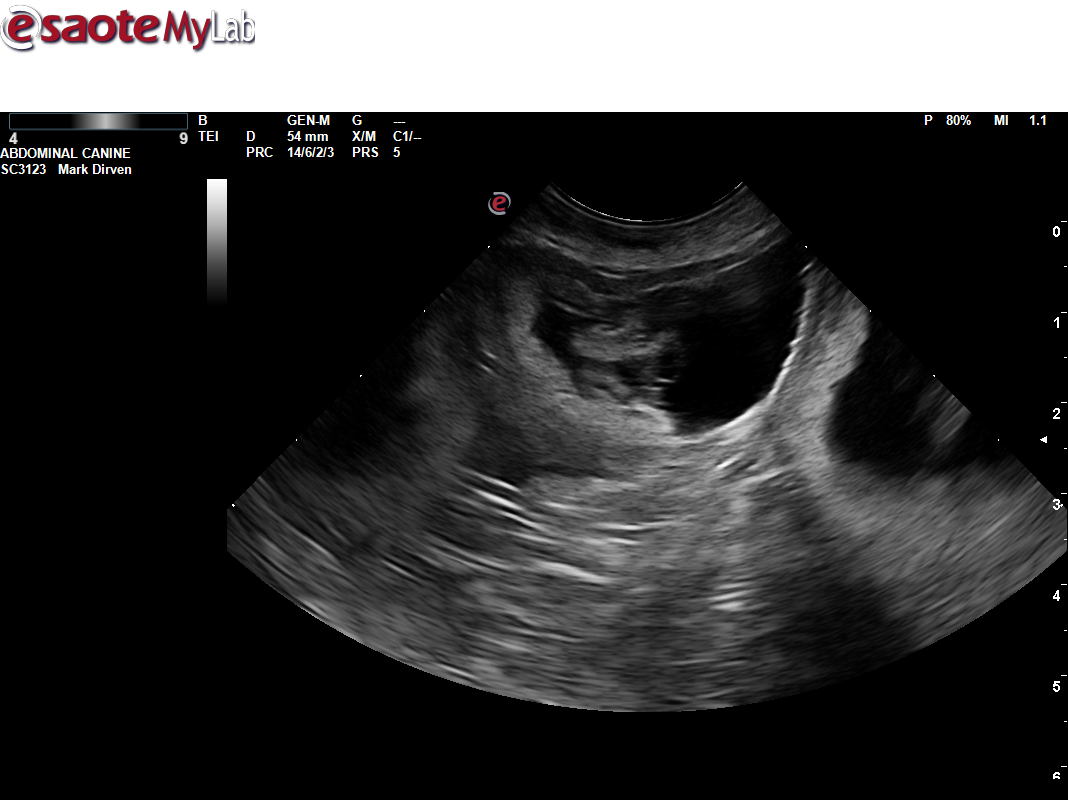

Uitslag heupen Mayla

Mayla 4 september 2019 heupen HD A